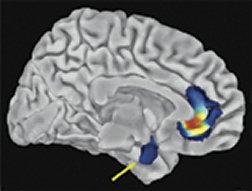

Scientists have for the first time seen what a genetic predisposition to depression looks like in the brain. Brain images show that people who inherit a short version of a particular gene have poor control over neural reactions to threats and stress.

BLUE BRAINS. In this brain image, colored areas denote various degrees of sparseness in the amygdala (arrow) and the cingulate (multicolored area) of people with a short serotonin-transporter gene.